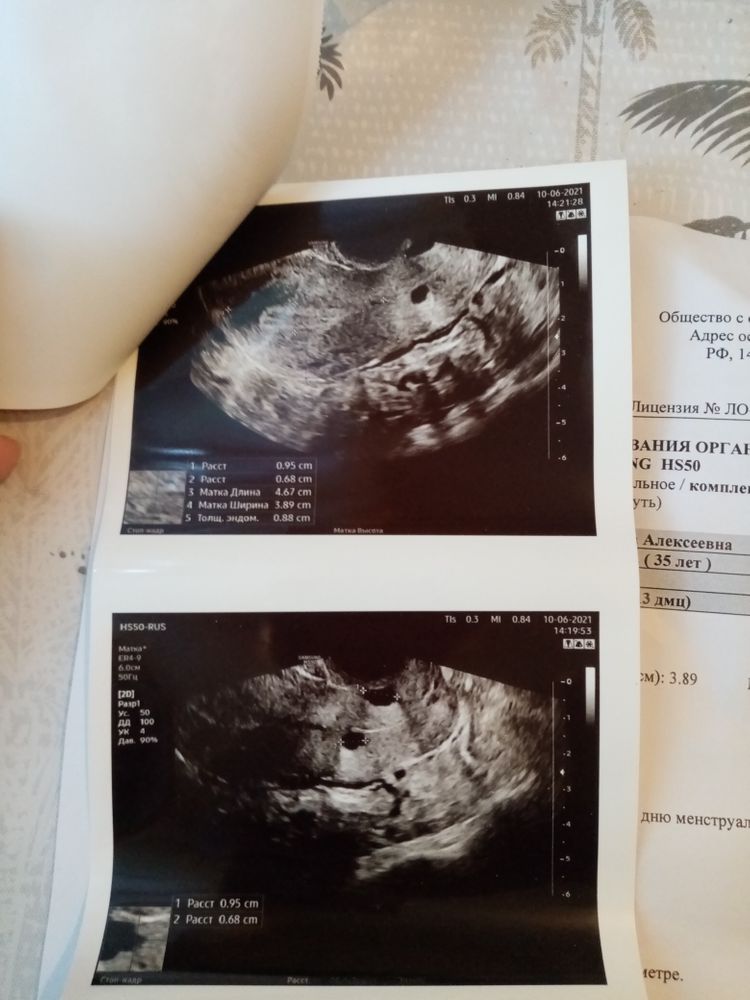

Вчера писала про ударную дозу укола хгч, так вот сегодня пошла на узи, получается 4 день после укола и мне сказали все лопнуло. Но вот когда О было, точно не сказала, сказало вот вот, возможно вчера. А можно по размерам ж. т узнать когда она была. Размер ж.т 21мм

Татьяна, Д.Ф был 20мм.Узистка сказала, что моё самолечение хорошо закончилась, что все там хорошо. И два раза повторила, что это точно не киста, а ж.т. Сказала что теперь только ждать и удачи пожелала

По жт трудно что то сказать. Вот про жидкость в пмп ничего не сказано, или я не увидела.. Да и какая разница когда была, ГЛАВНОЕ ЧТО БЫЛА!

Марина Сиреньщикова, про жидкость, она мне сказала что есть и даже показала. Я просто переживаю что секс был в день укола и через день, это вчера.